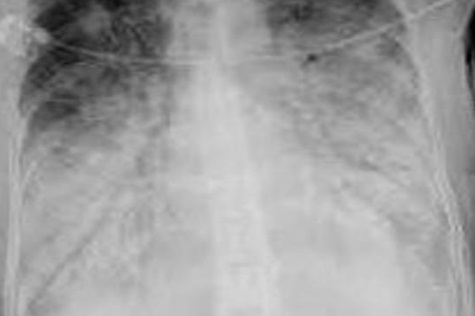

Q

¿Cuál es el diagnóstico?

A

Bronquiectasias